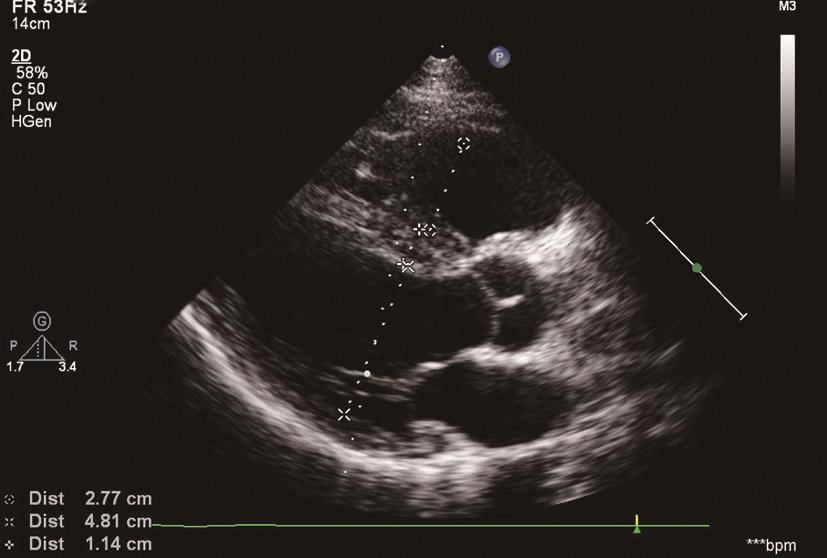

在左心室长轴切面、心尖四腔心切面及大动脉短轴切面,可显示右心房室内径增大,右心室壁厚度的增加>5mm、室间隔形状和运动的异常,左心室受压呈 “D”形(图6-2-1),右心室流出道增宽,主肺动脉及左右肺动脉内径扩张。

图6-2-1 右心室增大,左心室呈 “D”形

2.“D”形左心室

右心室压力或容量负荷过重,右心室的中心向左侧偏移,使室间隔自右向左心室的中心移动,室间隔变平,从而使左心室的短轴切面在收缩期呈现 “D”形。在这种情况下,左心室和右心室的形态关系,可用偏心指数来表示。偏心指数(eccentric index,EI),EI=D1/D2,D1表示与室间隔平行的左心室腔的前后径,D2表示从室间隔到侧壁的垂直于长径的短径。PAH特点:偏心指数>1。正常人:收缩期和舒张期EI均为1(左心室接近圆形)。异常的意义:舒张末期>1,表明右心室容量负荷过重,收缩末期和舒张末期>1,表明右心室压力负荷过重。分析室间隔的运动应在无合并严重传导阻滞的患者中进行,尤其应该避免那些合并左束支传导阻滞的患者。